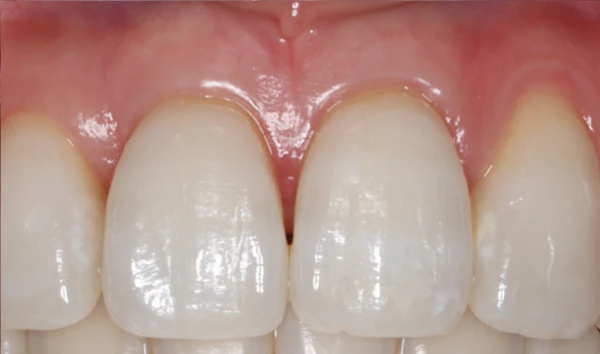

- 歯ぐきが下がって歯が長く見えます。治せますか?

歯周病で歯ぐきが下がると、歯根が露出し、見た目やしみる症状の原因になります。歯ぐきの移植(根面被覆術)などの治療で改善できる場合があります。